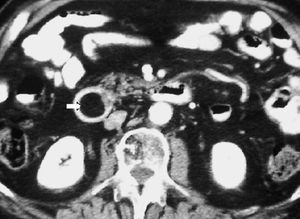

Una complicación tardía de la pancreatitis es el pseudoquiste. Puede localizarse en la pared duodenal, donde aparece radiológicamente como una lesión quística de paredes bien definidas, pudiendo producir una estenosis luminal (fig. 11).

Fig. 11--Pseudoquiste en pared duodenal. (A) Ecografía. (B) Tomografía computarizada en la que se aprecia una lesión quística (flecha) en la pared posterior de la tercera porción duodenal, que provoca compresión de la luz.